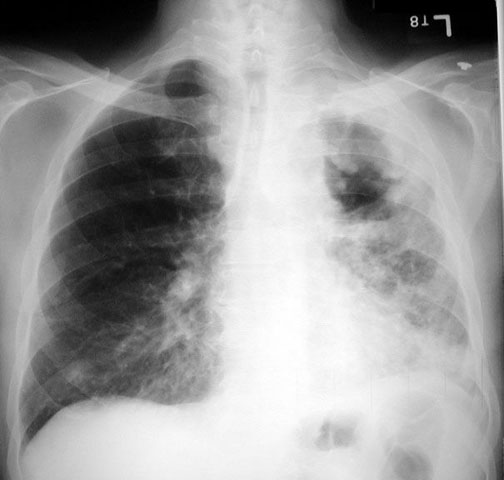

Case 2 Labeled Image What is the differential for multiple cavities?